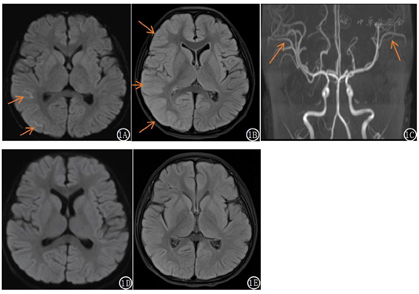

血乳酸、血氨、生化未见异常;血、尿氨基酸及有机酸代谢筛查未见异常;脑脊液常规有核细胞计数0.003×109/L;脑脊液生化均正常;甲状腺功能、甲状腺抗体阴性;24小时视频脑电图:背景活动慢(6~6.5 Hzθ波);血及脑脊液脱髓鞘病相关抗体(MOG、AQP4、GFAP、MBP抗体)均阴性;自身免疫性脑炎相关抗体(NMDA-R-Ab,AMPA1-R-Ab,AMPA2-R-Ab,CASPR2-R-Ab,LGI1-Ab,GABAR-Ab)均阴性;血和脑脊液寡克隆区带阴性;影像学检查见图1。

偏瘫型偏头痛患者发作期及发作后期脑脊液及头颅影像学检查大多是正常的,但重度脑病发作时头颅MRI可显示偏瘫对侧的脑水肿和弥散受限,可涉及整个大脑半球[11],也有一些头颅MRA显示可逆性的血管痉挛、扩张和缺血表现[15],症状缓解后上述影像也逐渐恢复正常。De Sanctis等[12]报道的相同变异位点患儿病程初期头颅MRI显示左侧大脑半球弥漫性皮质水肿及左侧额顶叶软脑膜强化,DWI完全正常,随着病情逐渐稳定,2个月后头颅MRI完全恢复正常。值得提醒的是,也有相关报道证实DSA检查可诱发偏瘫型偏头痛发作[16],故临床中需警惕。同时基因检测是诊断该病的金标准[11]。本例患儿急性期脑脊液检查均无异常,头颅MRI及MRA先后出现皮层肿胀、细胞毒性水肿以及大脑中动脉的分支增多,随着病情恢复,相关影像学检查也恢复正常。